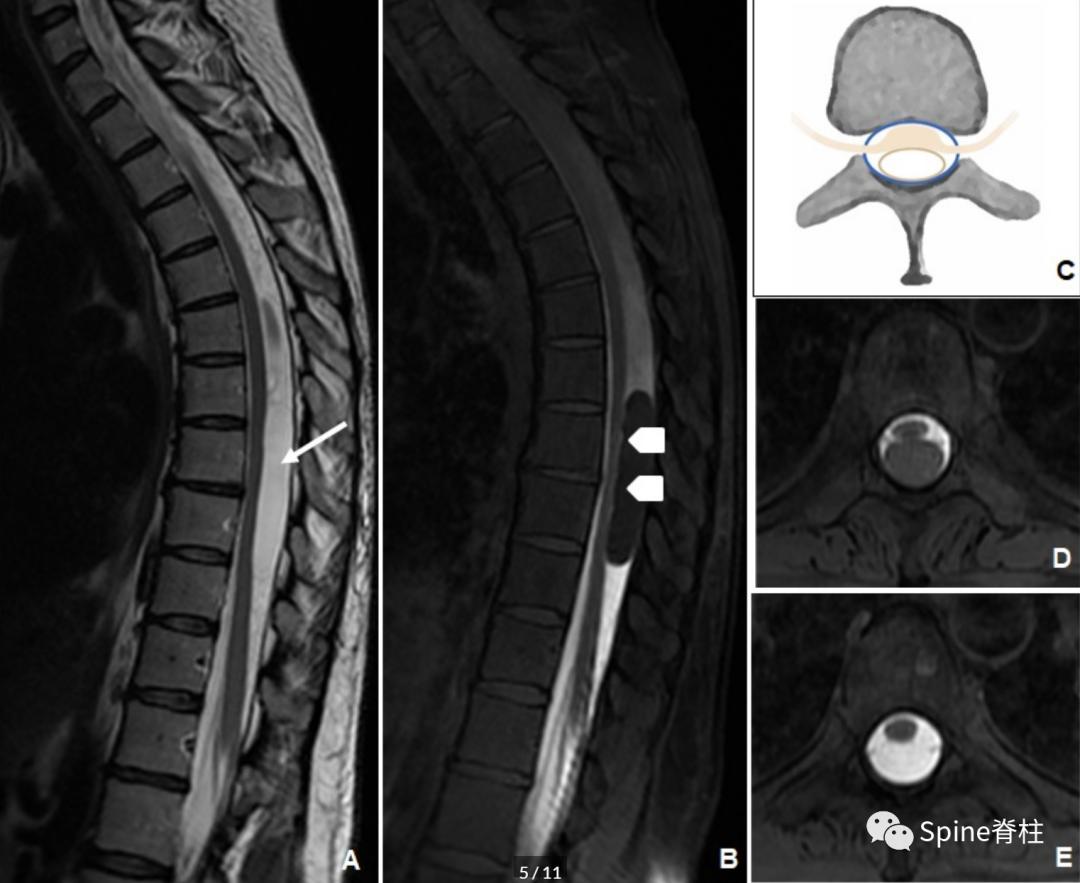

这些病变似乎是由蛛网膜小梁 (arachnoid trabeculae) 的改变引起的(主要是特发性的,但也可继发于以前的创伤、蛛网膜炎和手术)。大多数位于胸椎,最常见的临床表现为瘫痪、疼痛、步态共济失调和感觉减退。

在MRI上,常发现与脊髓压迫相关的脑脊液等信号硬膜内囊肿,脊髓表面有广泛的扇形凹陷。CT或MR脊髓造影很重要,因为这些病变通常比蛛网膜下腔的其余部分充盈更慢(下图)。治疗主要以囊肿完全切除为主。

胸椎硬膜内蛛网膜囊肿的MR脊髓成像。矢状位T2加权像提示与脑脊液相同信号的硬膜内囊肿伴脊髓受压移位(箭头,图A)。矢状位注射钆对比剂后早期抑脂T1加权像显示病变的确切位置,并显示脊髓表面的扇形压迹(箭头,图B)。 模式图显示了硬膜内蛛网膜囊肿的典型外观(C)。横断位蛛网膜腔注射钆剂后早期(D)和延迟(E)抑脂T1加权像序列显示囊肿缓慢钆剂充填。